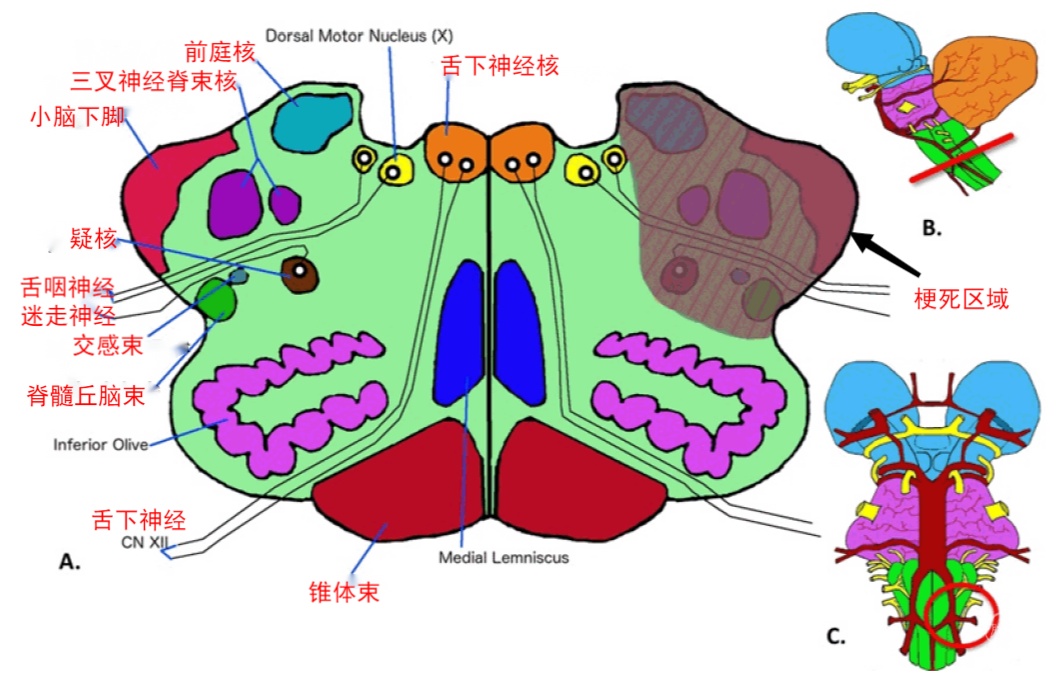

PICA小脑皮层支和脉络膜支与小脑上动脉(SCA)和小脑前动脉(AICA)吻合丰富,而延髓支吻合相对不足。因此,PICA梗死最常累及的缺血区域是由延髓分支供应的延髓背外侧。小脑后下动脉皮层段内侧干闭塞时可导致前庭小脑缺血梗死,引起眩晕、恶心、呕吐和姿势不稳。小脑后下动脉皮层段外侧干闭塞时引起辨距不良和同侧肢体肌张力下降。小脑后下动脉延髓支供血区域梗死引起延髓背外侧综合征(Wallenberg syndrome)。

图7 延髓背外侧主要结构:三核团(前庭核、三叉神经脊束核和疑核)、三传导束(脊髓丘脑束、交感纤维束、小脑下脚)和二神经(舌咽神经、迷走神经)。

图8 延髓背外侧综合征的临床表现(五大症状):①交叉性感觉障碍(三叉神经脊束核+脊髓丘脑束)、②眩晕+眼球震颤(前庭核)、③共济失调(小脑下脚)、④吞咽困难/咽反射减弱/构音障碍(舌咽神经+迷走神经+疑核)、⑤Horner征(交感传导束)。(A)绿线表示对侧上下肢(脊髓丘脑束)的痛温觉减退;黄线代表同侧上下肢(小脑下脚)共济失调。左侧面部紫色线表示同侧面部(三叉神经脊束核核)痛温觉消失。红圈代表同侧眼(交感传导束)的Horner综合征。(B)Horner综合征。左侧(同侧)上睑下垂、面部少汗/无汗症和瞳孔缩小。